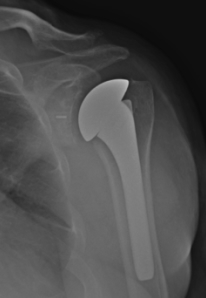

The picture on the right demonstrates bone spurs inside the shoulder joint. They indicate arthritis of the joint and are NOT NORMAL. The two locations have vastly different implications.

Far more people have bone spurs in their shoulder on the acromion (left picture) than inside the joint (right picture).